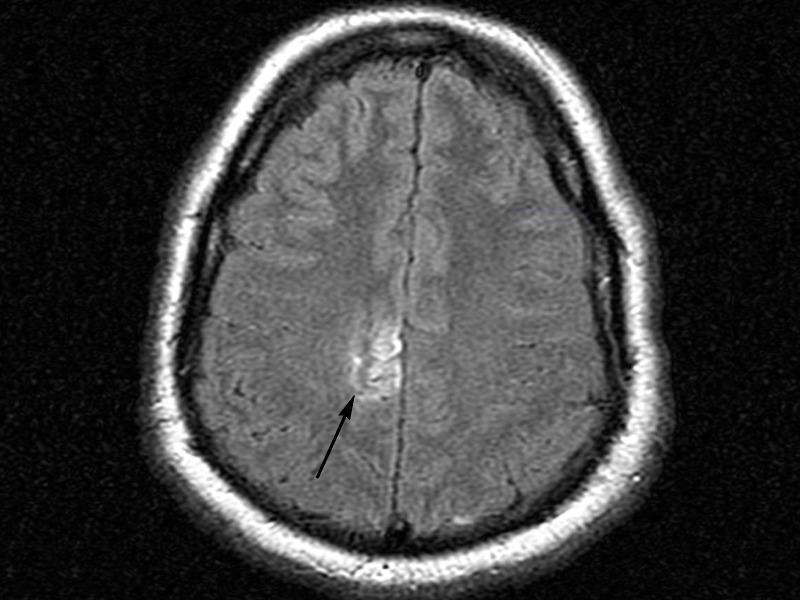

Spontaneous Thrombosis and Subsequent Recanalization of a Developmental Venous Anomaly.

Developmental venous anomalies (DVA) are among the most common congenital malformations of the cerebral angioarchitecture. Spontaneous thrombosis of this entity is rare, and our review of the literature found only 31 reported cases of symptomatic spontaneous thrombosis of developmental venous anomalies. Here, we report a unique case describing the spontaneous thrombosis of a DVA leading to venous infarction and subsequent recanalization. The patient was a previously healthy 21-year-old male who presented with an acute onset of partial seizures. Following negative hypercoagulability studies and along with CT (computed tomography) and MR (magnetic resonance) imaging, the patient was treated with anticoagulant therapy and demonstrated complete functional recovery. Knowledge from our literature review of similar cases combined with the experience gained from this patient's treatment leads us to suggest that spontaneous DVA thrombosis and venous infarction generally has a good outcome despite initially devastating neurologic deficits. Additionally, the rarity of spontaneous DVA thromboses lends itself to the need to identify possible predisposing risk factors, chief amongst these being hypercoagulopathies.